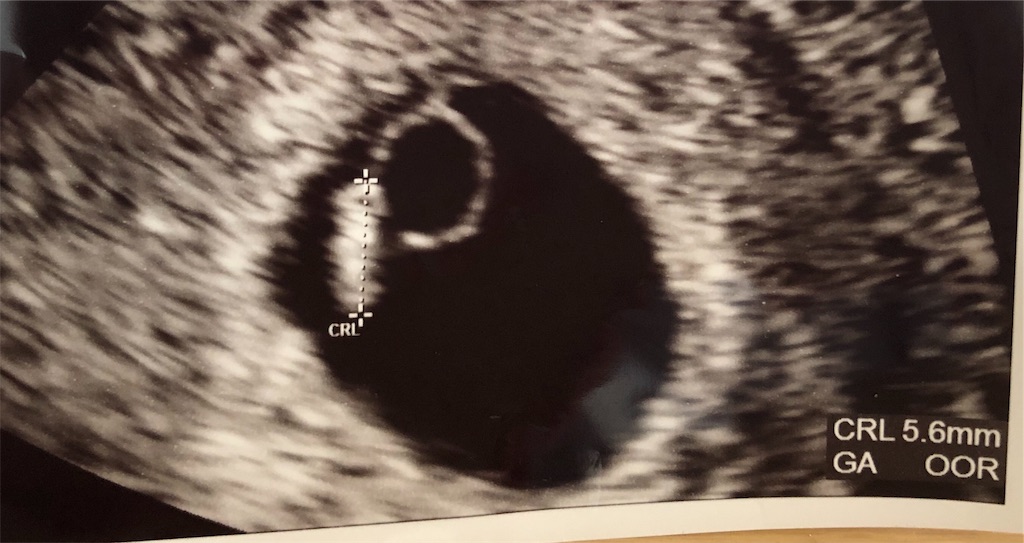

2019年4月27日 7w4d 無事心拍確認できました!

はじめて超音波検査の写真をもらえました。

この細長いのが赤ちゃんだそうです。

卵黄嚢(お弁当)にくっついてる。